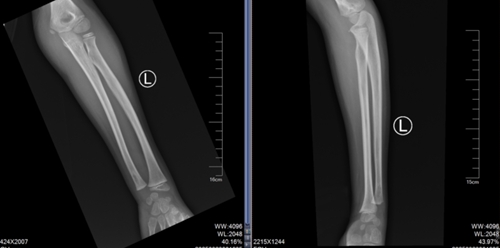

還有一名 10 歲男孩踢球時(shí)摔傷了右前臂,因腫脹疼痛無法活動(dòng),同樣來到了青島市婦女兒童醫(yī)院兒童骨折整復(fù)門診,尋求手法復(fù)位的幫助。經(jīng)門診醫(yī)生仔細(xì)評(píng)估,認(rèn)為孩子符合手法復(fù)位的條件,最終通過嫻熟的手法完成。這些孩子都成功避免了手術(shù),在無創(chuàng)治療下恢復(fù)了健康。

復(fù)位前

復(fù)位后